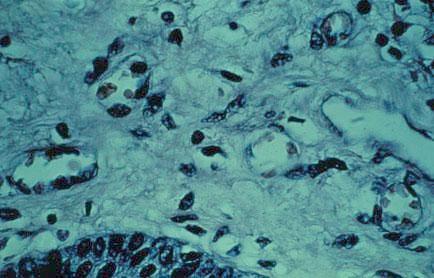

I-32 (4) K Slide 8. Extracellular matrix (ECM) containing blood vessels, fibers and connective tissue cells.